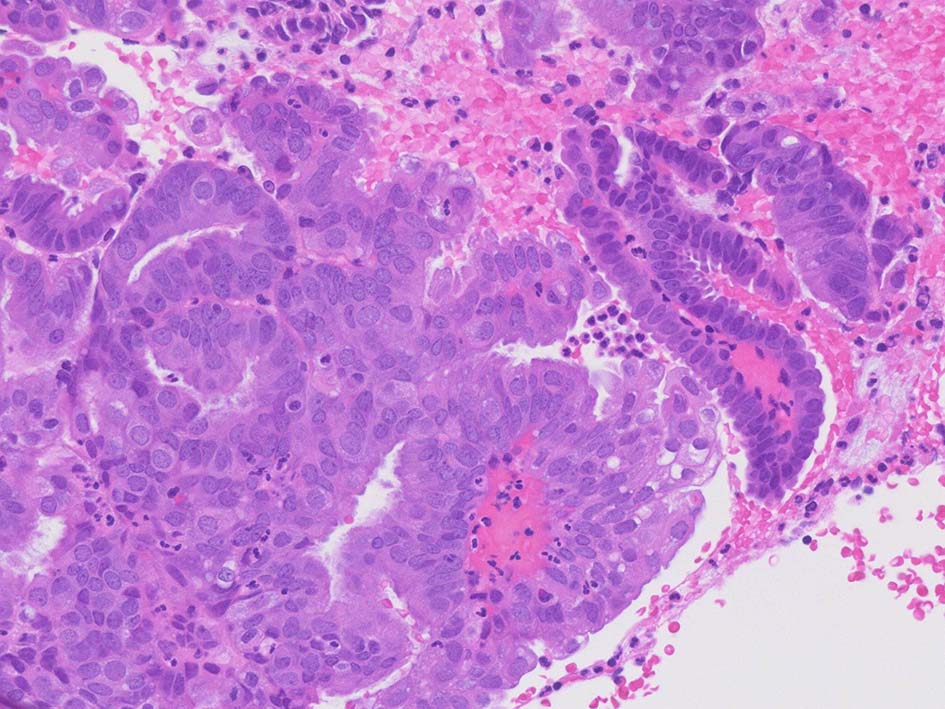

Case IWT-59yo woman

不正出血. ehoで子宮内膜の肥厚あり, CT,MRIでは子宮体部限局の体癌が疑われる. 内膜細胞診でClassIV.

Adenocarcinomaで内膜由来か頸管腺由来か判定困難. 子宮内膜全掻爬が行われた.

ER++, p53+, BCL2-, HER2-, p16は内膜化生上皮部分に陽性を呈した.

ARID1Aは正常内膜腺, 間質細胞, 浸潤リンパ球などが陽性に対して腫瘍細胞核はごく淡染あるいは陰性を示している. 低異型度内膜腺は核陽性(ARID1A_02)